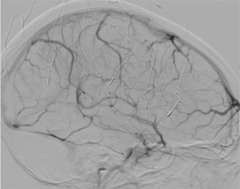

The blockage can result in brain swelling (edema), stroke, and/or bleeding in the brain (Figure 2).

Anticoagulation, the administration of a blood thinning drug is the first line of treatment and has been shown to be very effective. However, when the clot burden is too large and/or the patient condition deteriorates despite anticoagulation treatment, catheter based clot-busting treatment becomes a consideration (Figure 3).